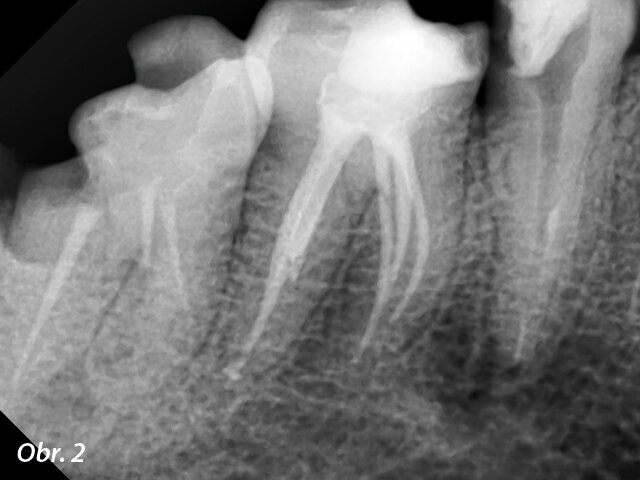

Podle našeho standardního postupu bylo endodontické ošetření započato izolací pracovního pole u zubu 46 kofferdamem. Dalším krokem bylo odstranění veškerého kariézního dentinu z postiženého zubu. Vstup do pulpální dutiny nám dal představu o skutečném rozsahu problému: obsah meziálních kanálků byl zcela nekrotický. Kromě toho bylo zajímavé objevit neobvyklý model kořene, který jsme na základě rentgenových snímků předpokládali. Meziálně excentrický rentgenový snímek ukázal, jak důležité je zhotovit rentgenové snímky z různých úhlů: snímek odhalil samostatný meziolingvální kořen a pomohl nám správně dimenzovat přístupovou kavitu (obr. 2). Důkladná preparace neobvyklého systému kanálků byla značnou klinickou výzvou. Rozhodli jsme využít flexibilní NiTi nástroje pro co nejbezpečnější a nejefektivnější čištění.

Preoperační rentgenový snímek zubu 46. Obr. 2: Meziálně excentrický rentgenový snímek s pěti viditelnými kořenovými kanálky.